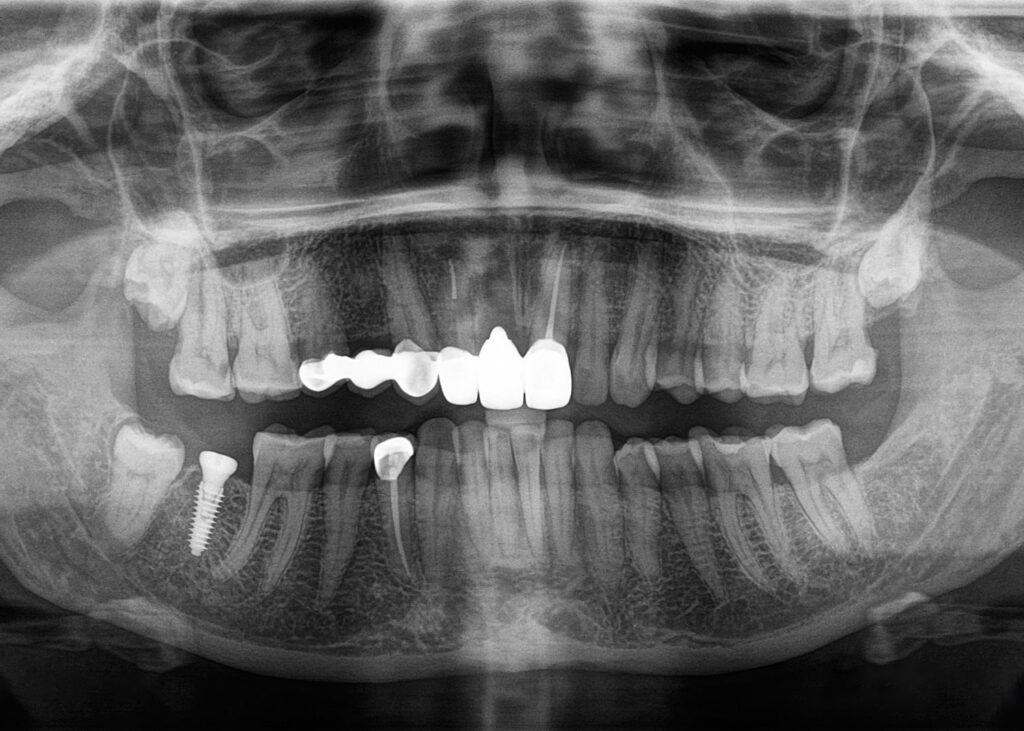

- Extraoral: Panoramic or full-jaw shots as needed

- Evaluating bone loss or gum disease

- Locating hidden (impacted) or remaining teeth

- Planning implants, root canals, or extractions

- Monitoring healing after surgery or treatment

- Tracking structural changes over time